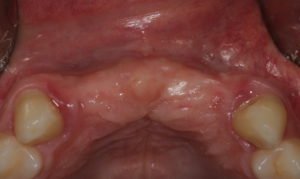

Paciente procurou a área de CBMF da Unicamp com a pré-maxila edêntula (Figuras 1 e 2) e foi submetido à técnica Screw Tent Poleutilizando os parafusos da linha Orth – Implacil de Bortolli (Figura 3). Do lado esquerdo da pré-maxila foram instalados três parafusos que apresentavam roscas em toda superfície, enquanto que do lado direito foram instalados três parafusos que não apresentam roscas no terço cervical (Figuras 4 e 5). Biomaterial associado com PRF (Stick Bone) foi adequadamente acomodado na região entre os parafusos e recoberto por membranas de PRF (Figuras 6 e 7). Uma sutura livre de tensão foi realizada para finalizar o procedimento cirúrgico (Figura 8).

figuras 1 e 2